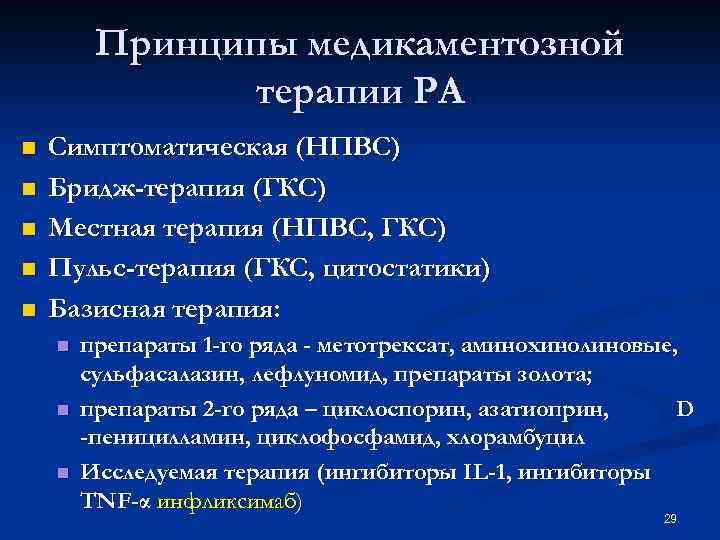

Принципы медикаментозной терапии РА n n n Симптоматическая (НПВС) Бридж-терапия (ГКС) Местная терапия (НПВС, ГКС) Пульс-терапия (ГКС, цитостатики) Базисная терапия: n n n препараты 1 -го ряда - метотрексат, аминохинолиновые, сульфасалазин, лефлуномид, препараты золота; препараты 2 -го ряда – циклоспорин, азатиоприн, D -пеницилламин, циклофосфамид, хлорамбуцил Исследуемая терапия (ингибиторы IL-1, ингибиторы TNF-α инфликсимаб) 29

Принципы медикаментозной терапии РА n n n Симптоматическая (НПВС) Бридж-терапия (ГКС) Местная терапия (НПВС, ГКС) Пульс-терапия (ГКС, цитостатики) Базисная терапия: n n n препараты 1 -го ряда - метотрексат, аминохинолиновые, сульфасалазин, лефлуномид, препараты золота; препараты 2 -го ряда – циклоспорин, азатиоприн, D -пеницилламин, циклофосфамид, хлорамбуцил Исследуемая терапия (ингибиторы IL-1, ингибиторы TNF-α инфликсимаб) 29